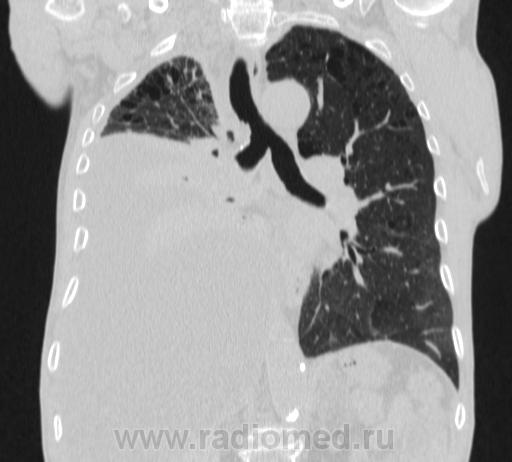

Пожилой мужчина, лечился по н/д правостороннней пневмонии в терап/отделении. Жалобы на одышку, кашель. По результатам Р-контроля после лечения направлен на КТ легких с диагнозом: плеврит справа, распад? В корне правого легкого вижу объёмное образование, с распадом. Смущают размеры плеврита,очень много жидкости, почти до 3 ребра. Анализы крови спокойные- L4,0-6,6, СОЭ 12-16мм. Неужто ТБС, отсев бы был при таком огромном поражении. В посеве мокроты-100% высев клебсиэллы пневмоние. Мокрота на общий анализ в работе-собирает с трудом, изза отсутствия мокроты. Плевральную пункцию еще не проводили. Н азначила бронхоскопию и плеврал пункцию. Как думаете, уважаемые коллеги, это онкопроцесс или тбс распад?

Не смотря дайкомы, только по рентгенограмме, предположил бы центральный рак правого легкого. Потому что большой гидроторакс, без смещения средостения в здоровую сторону, как правило, соответствует раковому ателектазу.

По-моему там и слева лимфаденопатия корня легкого, гидроторакс туберкулезной этиологии редко у пожилых бывает

Небольшое количество увеличенных лимфоузлов, и те - не сказать, чтоб были очень крупными. От эмпиемы до онкологии... Умеренное количество жидкости в перикарде, толщиной слоя до 13-14 мм. При подобной картине не вижу смысла гадать по сжатому лёгкому, пишу так: массивный выпот справа, около 2500 мл, диафрагма оттеснена жидкостью каудально, печень (!!!) смещена каудально и вправо. Легкое справа значительно компрессировано жидкостью, оценка проходимости бронхов и состояния легочной паренхимы (кроме имеющейся эмфиземы) практически невозможна. Необходима пункция плевральной полости справа (цитология, ВК, посев на микрофлору и проч), КТ-контроль после эвакуации жидкости.